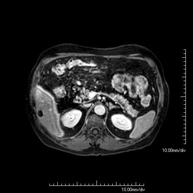

- RM d'Abdomen

Prova diagnòstica no invasiva que consisteix en l'obtenció d'imatges d'alta definició anatòmica de l'abdomen mitjançant l'ús d'un camp electromagnètic i ones de ràdio (amb un emissor i un receptor). No utilitza radiació ionitzant. En aquesta exploració s'inclouen el fetge, el pàncrees, la melsa, la via biliar, la vesícula biliar, les glàndules suprarenals, els ronyons, l'aorta abdominal, la vena cava inferior, l'estómac, el duodè, etc. En alguns casos caldrà emprar contrast paramagnètic (Gadolini) per caracteritzar les lesions. - RM Pelvis femenina